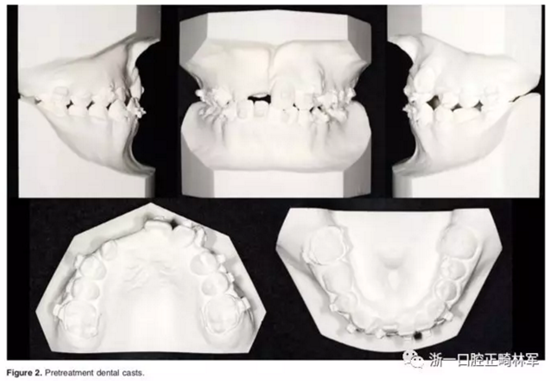

口內(nèi)相示:替牙晚期,11-13未萌,磨牙端端關系,前牙擁擠嚴重,23高位,53、75滯留;患者正采用固定矯治,部分托槽有脫落。

全景X片及CBCT示:11-13復雜阻生,上頜前牙區(qū)牙槽骨水平不足;11阻生,遠中旋轉(zhuǎn)90°,牙冠朝向腭側,根尖位于鼻底、前鼻棘皮質(zhì)骨內(nèi),牙根形態(tài)彎曲;12、13不完全易位,12位置偏腭側,13位置偏舌側,12的牙根形態(tài)也較彎曲。

診斷:骨性I類,牙性II類,高角,多牙阻生,面部不對稱(右偏),上下切牙直立。